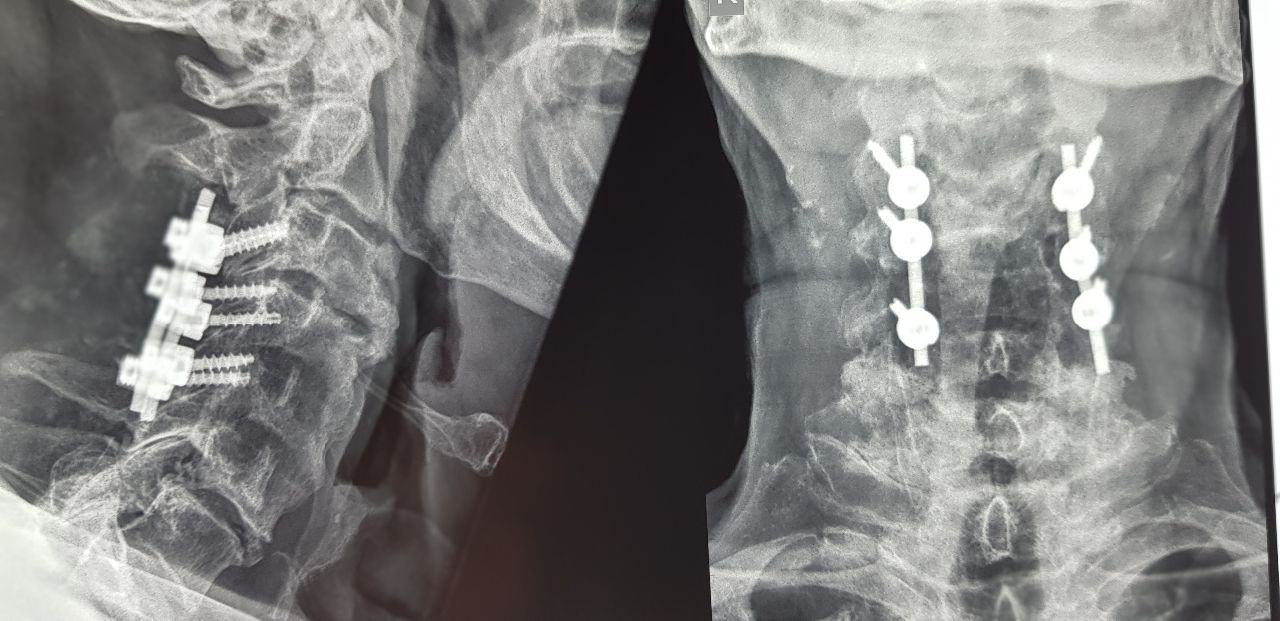

Οπίσθια αυχενική σπονδυλοδεσία πλαγίων ογκωμάτων και πεταλεκτομία σε εκτεταμένη μυελοπάθεια.